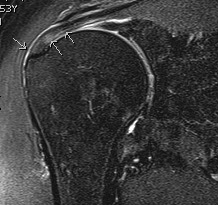

MRI

Articular Sided / PASTA (partial articular sided tendon avulsion)

Bursal Sided